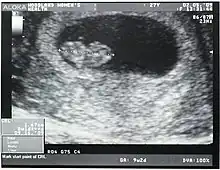

Crown-rump length (CRL) is the measurement of the length of human embryos and fetuses from the top of the head (crown) to the bottom of the buttocks (rump). It is typically determined from ultrasound imagery and can be used to estimate gestational age.

The embryo and fetus float in the amniotic fluid inside the uterus of the mother usually in a curved posture resembling the letter C. The measurement can actually vary slightly if the fetus is temporarily stretching (straightening) its body. The measurement needs to be in the natural state with an unstretched body which is actually C shaped. The measurement of CRL is useful in determining the gestational age (menstrual age starting from the first day of the last menstrual period) and thus the expected date of delivery (EDD). Different human fetuses grow at different rates and thus the gestational age is an approximation. Recent evidence has indicated that CRL growth (and thus the approximation of gestational age) may be influenced by maternal factors such as age, smoking, and folic acid intake. Early in pregnancy gestational age 8 weeks, it is accurate within about +/- 5 days but later in pregnancy due to different growth rates, the accuracy is less. In that situation, other parameters can be used in addition to CRL. The length of the umbilical cord is approximately equal to the CRL throughout pregnancy.